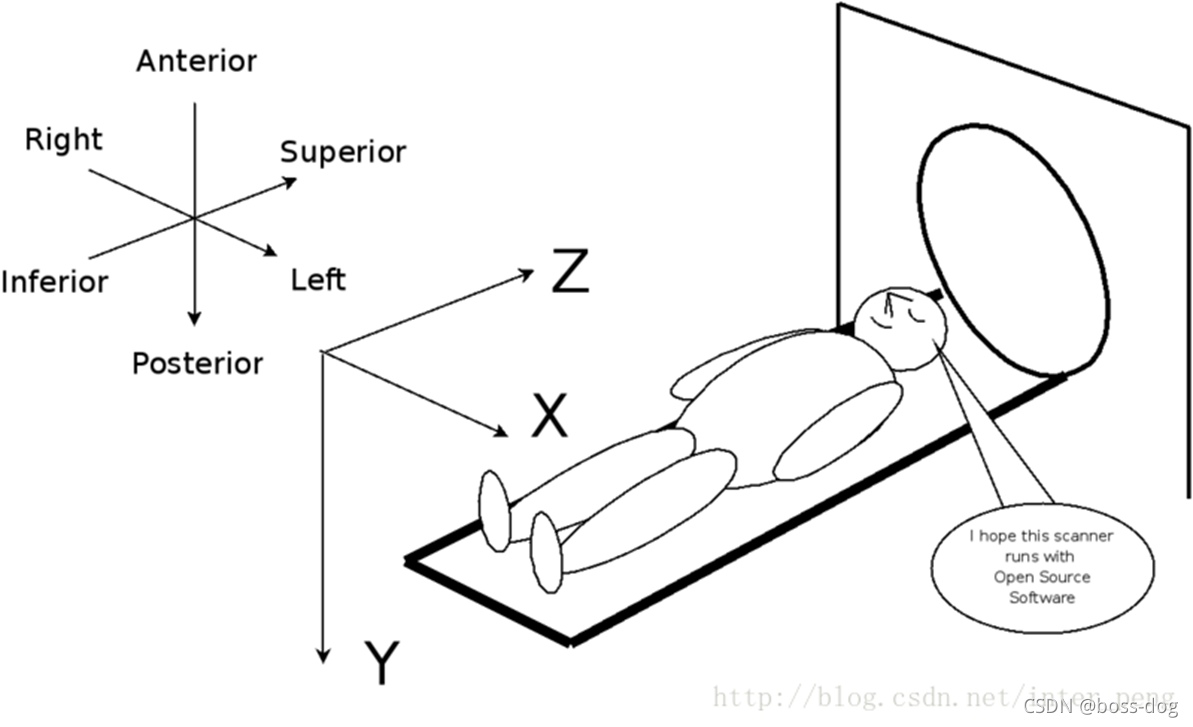

Image Orientation-2

(0018,5100) Patient Position简单描述了病人和影像设备之间的位置关系,以一个不超过16个字节的字符串存放。信息定义如下:

第一个字母H(head)和F(feet)表示是病人的头先钻到影像设备里面还是脚先钻到影像设备里面。

P(prone)和S(supine)表示是仰躺着进影像设备还是趴着进影像设备,Decubitus表示侧卧

- HFP = Head First-Prone

- HFS = Head First-Supine

- FFP = Feet First-Prone

- FFS = Feet First-Supine

- HFDR = Head First-Decubitus Right

- HFDL = Head First-Decubitus Left

- FFDR = Feet First-Decubitus Right

- FFDL = Feet First-Decubitus Left

这个数据元素并不是很精确的描述病人和影像设备之间的数学关系,只是为了设定一个坐标系的方向。

Image Orientation-3

- (0020,0032) Image Position (Patient)描述了该张影像首个像素(“左上方”)的坐标,这个数据元素和(0020,0037)一起确定了该张影像中所有像素的坐标,用3个不超过16字节的字符串存放。分别是X,Y,Z值。

- (0020,0037) Image Orientation (Patient)是一个非常重要的数据元素。由6个不超过16字节的字符串存放。

在这里先要说明一下,在DICOM 3.0中坐标轴的指向完全以病人为准。以病人中心为原点,病人左手指向的方向为X轴正向,病人背后的方向为Y轴的正向,往病人头部的方向为Z轴的正向。因此是一个以病人为中心的右手坐标系。